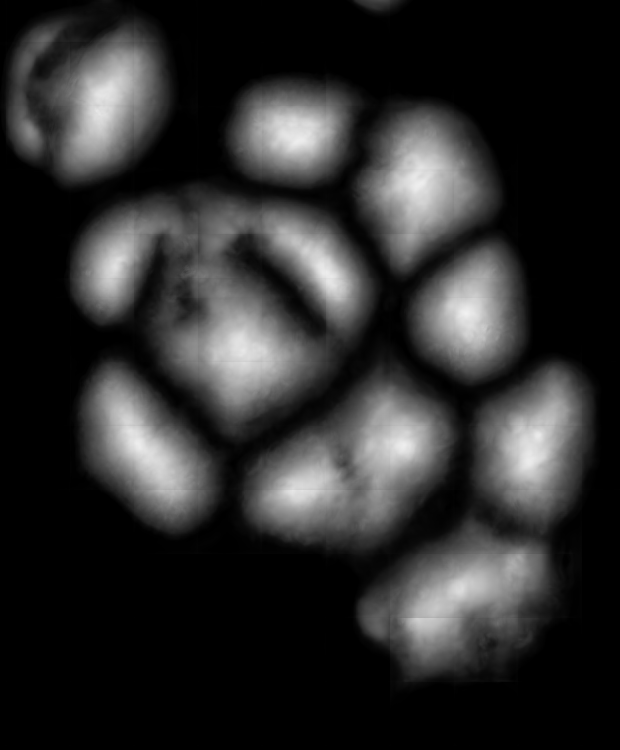

Since the main goal of this work is cell detection, our DeepDistance models define the estimation of an inner distance map as the main task and find regional maxima on this estimated map to detect cells. The motivation behind these choices is the fact that the inner distance definition gives sharp increases at cell centers and the locations with these sharp increases can be detected by finding regional maxima. Hence, to obtain accurate detections, one should estimate an inner distance map with distinct differences between the cell centers and their surrounding pixels such that these centers can be identified as regional maxima. That is, one should estimate a map consisting of sharp enough bright regions close to the cell centers. To improve the performance of the task of this inner distance estimation, our models take advantage of multi-task learning approach. This approach helps the models become more robust to avoid overfitting a task, compared to the approach of learning the same task alone with a single-task model (Caruana, 1997). To get more insight in this multi-task learning approach, this section visually analyzes the estimated maps of single-task and multi-task models.

![]() |

| (a) | (b) | (c) | (d) |

For the independent test samples given in Fig. 4, Fig. 6a shows the maps of the calculated inner distances when the ground truths are given. Figs. 6b, 6c, and 6d illustrate the inner distance maps estimated by the SingleInner method, the proposed DeepDistance model, and its extended version, respectively. SingleInner learns its map as a single-task whereas our models define auxiliary tasks and learn the inner distance map in parallel to these auxiliary tasks, forcing them to learn shared representations with a shared encoder path. The latter type of learning, which is an example of multi-task learning, is known to be effective for increasing the performance of individual tasks for many domains. We also observe this performance increase in the estimated maps given in Fig. 6. SingleInner cannot successfully detect the three cells shown inside red ellipses since it cannot produce sharp enough bright regions (with distinct enough estimated distances) for these cells. Although DeepDistance, which uses one auxiliary task, leads to brighter regions for these cells, they are still not sharp enough for two of them to be identified as regional maxima. The extended version of DeepDistance, which uses one more auxiliary task, does better job in inner distance estimations such that they have sharp enough bright regions for all of these three cells.

In this figure, it is worth to noting two points: First, all methods apply the h-maxima transform on their estimated maps beforehand to suppress noise, and hence, to prevent over-segmentations and false positives. If it was not applied, SingleInner might give regional maxima for some of the three cells even though the distances estimated for their centers were not that distinct (bright). However, that case would also give many over-segmented cells and false positives. Second, none of the methods identify the cell shown inside a blue ellipse although their estimated distances yield bright regions for this cell. It is due to the evaluation method, which matches an annotated marker and a detected cell based on the distance between them since a test set image does not have boundary annotations but just a dot on each cell. In our experiments, a distance threshold is set to 30, considering image resolutions and the average cell size. This threshold may give a few incorrect matchings especially for larger cells, (e.g., the cell shown inside the blue ellipse). Increasing this threshold solves the problem for this particular cell, but this time, it will result in many incorrect matchings of detected cells with distant markers (or vice versa).